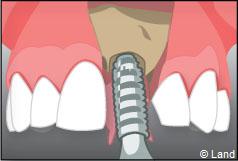

Exemple d’un implant unitaire pour remplacer une dent antérieure manquante.

Le chirurgien-dentiste après une anesthésie locale pratique une incision, puis il décolle la gencive pour accéder à l’os alvéolaire.

Ensuite il prépare l’emplacement de l’implant dans l’os en passant plusieurs forets de diamètre croissant. Le forage de l’os se fait à vitesse maîtrisée et lente sous irrigation, pour respecter la structure osseuse et éviter tout échauffement de celle-ci. Le praticien arrête lorsqu’il a obtenu un puits d’un diamètre très légèrement inférieur à l’implant à poser.

L’implant est placé dans l’os le plus souvent par vissage et doit avoir une liaison forte avec l’os. Le praticien replace alors la gencive et pose des points de suture.